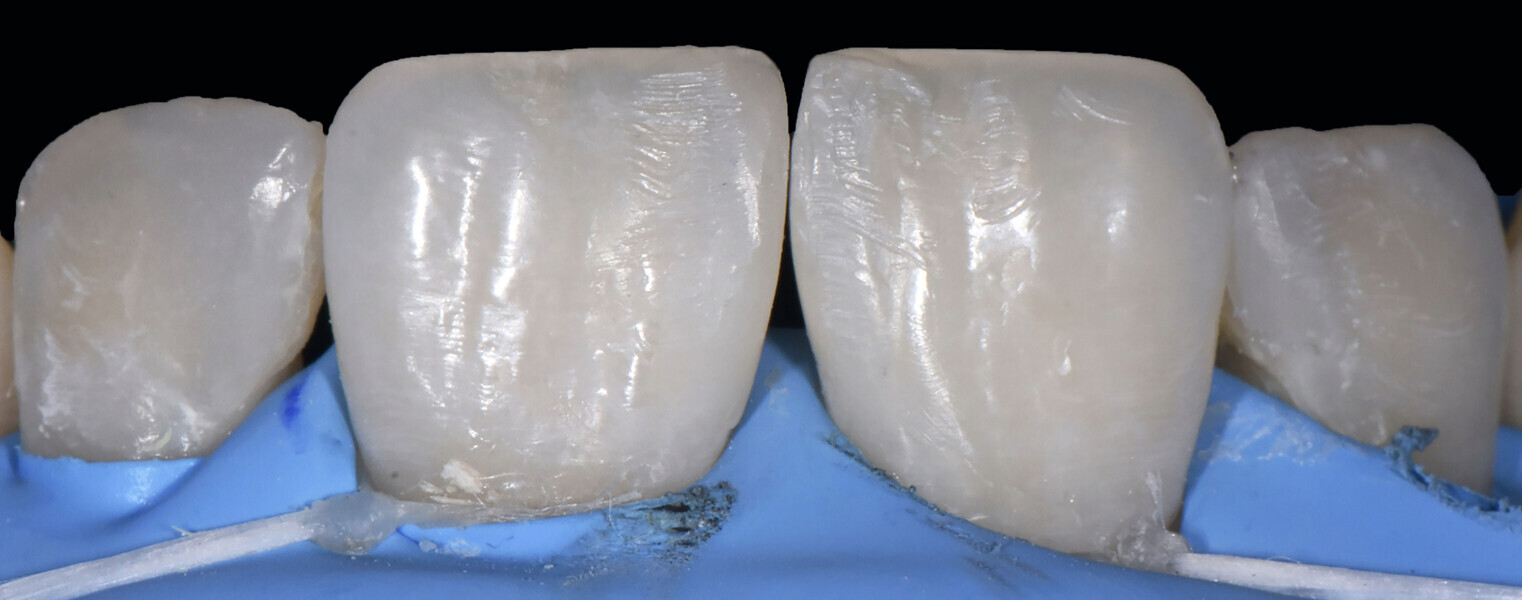

We followed a thorough analysis of the chromatic spectrum, as described by Naorungroj, to accurately and precisely establish the shades to be used in the operative steps (Fig. 2).1 The photographic material was carefully analysed to determine the ideal work planes to gain the information required to achieve the ultimate aesthetic aim of the treatment.

Figs. 2a–d: Choice of shade values.